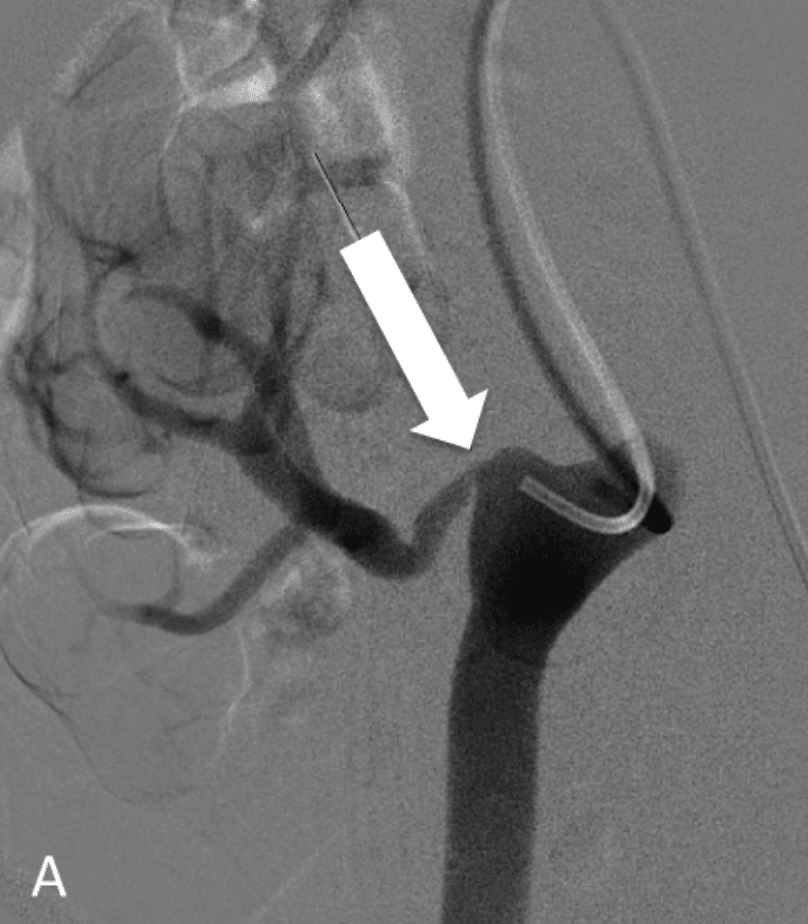

Stenting procedure. A, Angiogram showing right external iliac artery Renal Artery Stent Surgery Technical aspects of renal artery stenting are addressed, including methods to avoid procedural complications and use of embolic protection. Medications may help manage hypertension, but if the stenosis is severe and causing resistant hypertension, surgery may be. There was a trend for higher levels of bnp in blood pressure responders (bnp=202�240) compared with patients who did not respond (bnp=85�89, p. Renal Artery Stent Surgery.